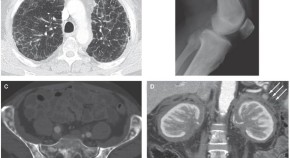

• Erdheim–Chester disease is a rare form of non-Langerhans cell histiocytosis characterized by foamy histiocyte infiltration of the skeleton and viscera. A case of Erdheim–Chester disease that was initially mistaken for Ormond's disease is presented with a discussion of the tests required to differentiate between the two diagnoses.